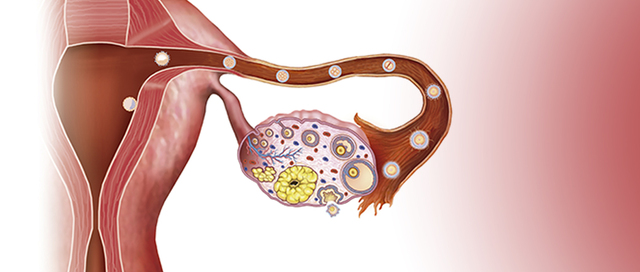

• Ovulación

Ovulación

El óvulo comienza a desplazarse a través de la trompa de Falopio que lo conduce hacia el útero. Alrededor de estos días, si un espermatozoide fecunda un óvulo y éste se adhiere a la pared del útero se inicia un embarazo.

• Fecundación

Fecundación

La información genética de el óvulo y el espermatozoide se van a reorganizar uniéndose y formando un nuevo núcleo celular compuesto por 46 cromosomas.